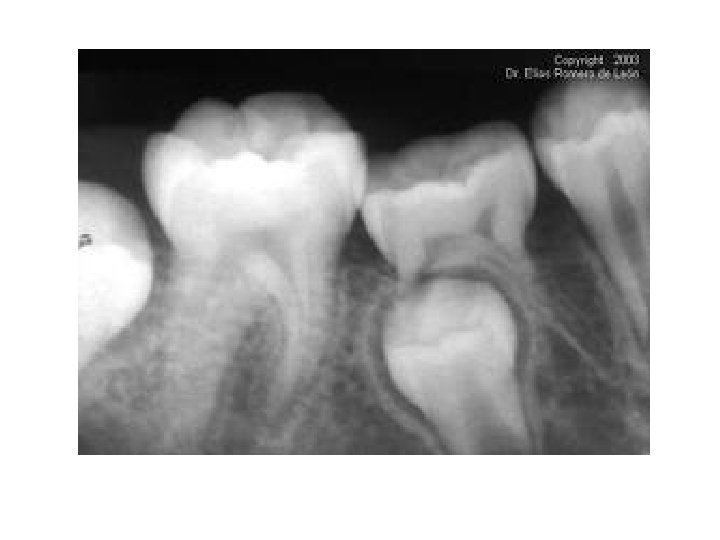

• GINGIVITIS: • es una enfermedad bucal generalmente bacteriana que provoca inflamación y sangrado de las encías, causada por los restos alimenticios quedan atrapados entre los dientes. Es muy frecuente que su origen sea causado por el crecimiento de las muelas del juicio, que produce una concavidad, que es donde se deposita el agente patógeno o bacteria. Esta enfermedad se puede desarrollar después de tres días de no realizar la higiene oral (cepillado de dientes y lengua). Cuando esta enfermedad evoluciona a un estado crónico, provoca bolsas periodontales, movilidad dentaria, sangrado excesivo y espontáneo, y pérdida del hueso alveolar que sostiene a los dientes, con la gran posibilidad de perder piezas dentales.